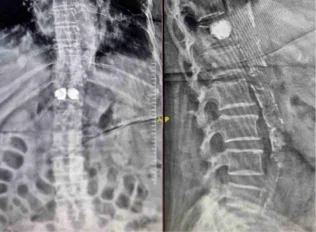

Before & After Clinical Gallery

We showcase real patient cases (with consent), including:

- Pre- and Post-operative MRIs and X-rays

- Disc Herniations, Stenosis, and Spondylolisthesis cases

- Visible improvement in alignment and decompression